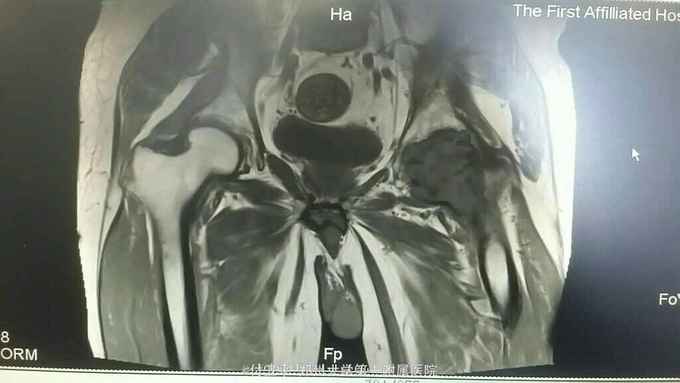

患者,男,51岁。 主诉:左髋部疼痛2年余 病史:患者2年前无明显诱因出现左髋部疼痛,就诊于北京某医院,诊断为:左侧股骨头坏死,给予中成药及汤药治疗(具体不详),效差。至我院门诊行MRI,考虑:左侧股骨头富血供病变,考虑恶性可能,不排除炎性病变可能。遂收入我科进一步明确诊断。

查体:左髋部压痛、叩击痛,左髋关节活动轻微受限,左髋关节4字试验阳性,余查体未见明显异常。 辅助检查:全身骨显像回示:左侧髋关节及左侧股骨近端骨代谢异常,考虑骨恶性病变。左膝关节及左侧胫骨近端骨代谢异常活跃,考虑骨良性病变。增强磁共振回示:左髋关节富血供病变,考虑恶性病变。肺CT未见明显异常。双下肢深静脉彩超回示:左下肢股总静脉、股浅静脉、腘静脉、胫后静脉、腓静脉血栓形成。